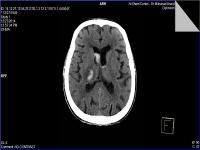

(#0172) CT Hypertensive ICH with Intraventricular Extension